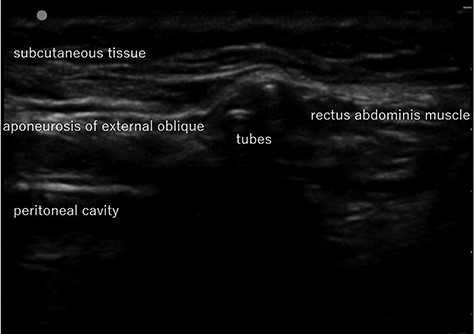

Abdominal US image in Case 1: US showed the tubes running under the aponeurosis of the external oblique that is the anterior wall of the inguinal canal.

computed tomography (CT) showed right IH and a balloon that was placed by the bladder and a connecting catheter that went through the lateral side of the rectus abdominis muscle (Fig. 2). In the operation, we performed ultrasonography (US) at first and it demonstrated that the catheter was running through the inguinal canal (Fig. 3). When we incised the aponeurosis of the external abdominal oblique muscle, the catheter of the AUS was observed in the inguinal canal (Fig. 4). We identified the hernia sac protruding from the inguinal ring and diagnosed it as an indirect IH. The adhesion was too hard to separate the catheter from the pubis and posterior wall of the inguinal canal around pubis. Then, the IH was repaired using the Lichtenstein technique; however, the mesh near the pubis could not be spread as ordinarily.

There is a report that contraindicates the laparoscopic repair for IH because of scaring and adhesion after RP in the preperitoneal space [4]. In addition, it is difficult to avoid damage to the AUS device without tactile perception. Therefore, we chose an anterior approach, which is the most familiar method for us. The operation of Case 1 patient was difficult because of adhesion in the inguinal canal, but Case 2 was not. The difference between the two cases was whether the catheter went through inguinal canal or not. We could detect the tract of the catheter by preoperative CT and US, which could be a good predictor for adhesion or difficulty in the operation.